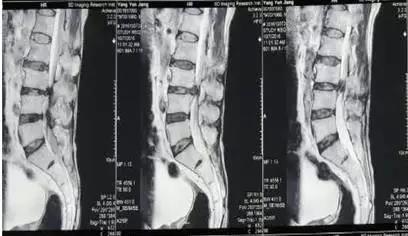

4月前无明显诱因出现腰痛伴双下肢无力,无法站立行走并出现大小便困难,大便8天未解,服用通便药物无效。当地医院腰椎MR检查显示椎管内分叶状占位,性质待定。遂来我院就诊,以“腰椎间盘突出症”收住疼痛科,行经皮腰椎间孔镜髓核摘除术。

手术经过:轮椅推入手术室,取府卧位,腹下垫软枕,C形臂X线透视确定L4/5左侧小关节内侧缘为穿刺进针点并标记,洗手穿手术衣,常规消毒,铺治疗巾,给病人保护套,铺大洞巾,局麻(2%利多卡因10ml,20ml生理盐水)皮丘5ml,从穿刺点进针后,C臂调整针正位位于L4/5左侧小关节内侧缘,侧位位于L4/5椎间盘内,推注1ml造影剂,透视确认位置,放置导丝,手术刀片切皮,六级扩张管逐级扩张后放工作套管,透视确认位置正确,连接各种线路(镜头视频线、光源线、水管、手柄电极)并固定,调整镜头焦距,测试电极强度,镜子确认位置,发现硬膜囊受压,初步清理蓝染的髓核,逐渐分辨神经要、硬膜囊及后纵韧带,各个方向清理突出变性髓核、射频电极止血。解除压迫以后,硬膜囊、神经根颜色由苍白变为红润,博动良好,以双极射频消融、止血、修整纤维环裂口,以使皱缩成形,电转磨除部分增生的上关节突,扩大椎间孔。退出工作套管缝合切口,无菌敷贴贴穿刺点,术中患者生命体征平稳,术毕患者腰背部疼痛及双下肢无力消失。